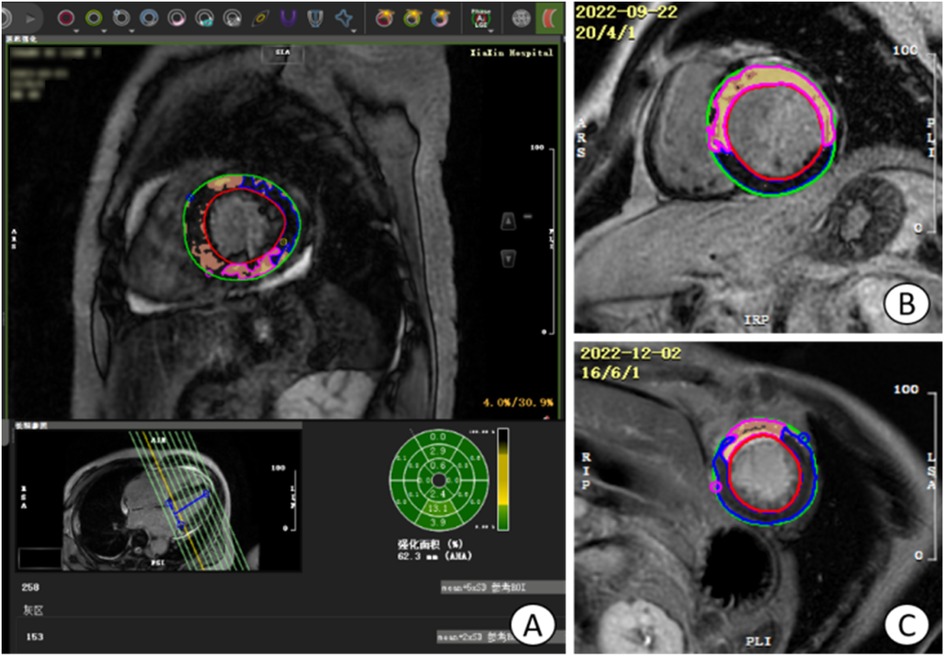

Figure 2

Manual measurement of apical angle on LGE image. (A,D) Patients with non-ventricular wall aneurysms, the apical angle is 82.93°; (B,E) patients with early ventricular wall aneurysms, the apical angle is 113.40°; (C,F) patients with early ventricular wall aneurysms with appendage thrombosis, the apical angle is 115.12°. The yellow markers show the apical angle. LGE, delayed gadolinium enhancement.